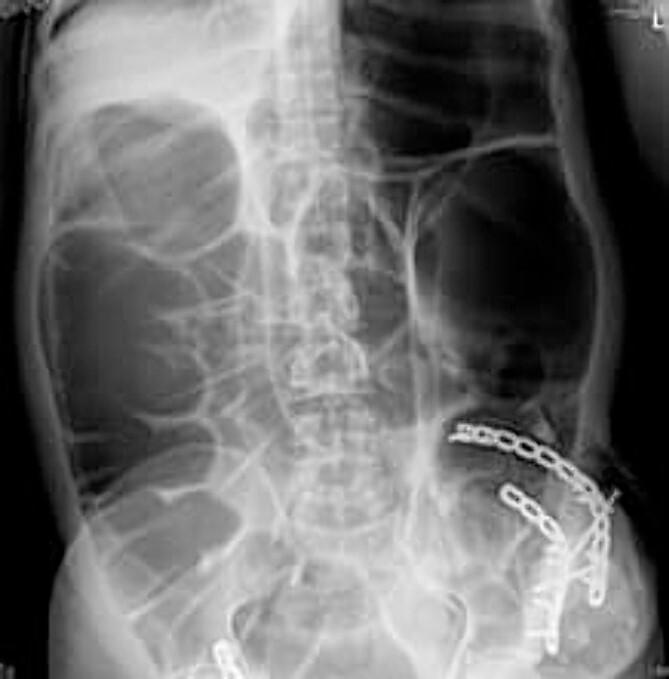

A previous surgical incision can lead to an abdominal wall defect known as an incisional hernia. The protrusion of abdominal viscera, particularly bowel loops, through this defect can result in various complications and affect organ function. Bowel loops are frequently involved and can lead to incarceration, obstruction or even strangulation. A 38-year-old male with a history of open reduction internal fixation for the left iliac wing presented with abdominal pain, vomiting and obstipation. Abdominal examination revealed a tender, distended abdominal area with swelling on the left hip. Radiological examination revealed bowel obstruction at the previous surgery site. During surgery, an incisional hernia was confirmed, and the bowel was found viable. Incisional hernias can occur even many years after primary surgery and may remain asymptomatic until complications arise. Elective hernial repair is recommended in some cases, such as the one presented here, as complications can be fatal.

既往手术切口可导致一种称为切口疝的腹壁缺损。腹腔内脏器,尤其是肠袢,通过该缺损突出可导致各种并发症并影响器官功能。肠袢常受累,可导致嵌顿、梗阻甚至绞窄。一名38岁男性,有左侧髂骨翼切开复位内固定病史,出现腹痛、呕吐和便秘。腹部检查发现腹部压痛、膨隆,左髋部肿胀。影像学检查显示既往手术部位肠梗阻。手术中证实为切口疝,发现肠管存活。切口疝甚至可在初次手术后多年发生,在并发症出现之前可能一直无症状。在某些情况下,如本文所述病例,建议择期进行疝修补术,因为并发症可能是致命的。